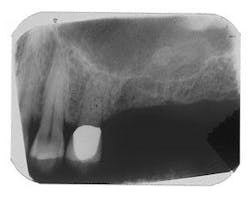

Figure 11 - Patient with insufficient bone below the sinus for implants

Figure 12 - CT scan demonstrating insufficient bone for implants (SimPlant software)

Figure 13 - Simultaneous sinus lift using autogenous bone plus Perioglas and ITI implant placement